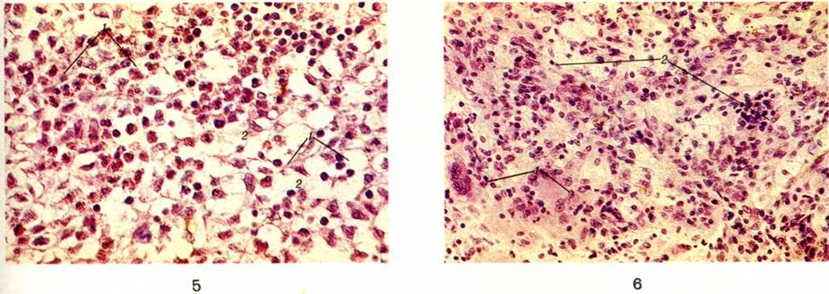

Хенда — Шюллера — Крисчена болезньХенда — Шюллера — Крисчена болезнь (A. Hand, американский педиатр, 1868 — 1949; A. Schuller, австрийский невропатолог и психиатр, 1874 — 1958; Н. A. Christian, американский врач, 1876 — 1951; синонимы: липоидный гранулематоз, болезнь Крисчена — Шюллера, липогранулематоз, хронический системный прогрессирующий гистиоцитоз) — болезнь из группы гистиоцитозов X, характеризующаяся инфильтрацией различных органов и тканей атипичными гистиоцитарными элементами. Заболевание впервые описал Хенд в 1893 год; он наблюдал у трёхлетнего ребёнка поражения кожи, костей черепа, увеличение печени и селезёнки. Шюллер (1916) и Крисчен (1919) выделили триаду симптомов при этой болезни: дефекты плоских костей, экзофтальм (смотри полный свод знаний) и несахарный диабет (смотри полный свод знаний: Диабет несахарный). В 1953 год Л. Лихтенстайн предложил термин гистиоцитозы X, объединяющий болезнь Хенда — Шюллера — Крисчена, болезнь Леттерера — Сиве (смотри полный свод знаний: Леттерера — Сиве болезнь) и эозинофильную гранулему (смотри полный свод знаний). По классификации ВОЗ (1976), эти болезни относятся к опухолевым заболеваниям кроветворной и лимфоидной ткани, входящим в подгруппу хроническая моноцитоидная лейкемия и системные гистиоцитарные заболевания (смотри полный свод знаний: Гистиоцитозы). Заболевание наиболее часто встречается у детей в возрасте 4—5 лет, значительно реже у взрослых. Этиология и патогенез до конца не изучены. Ряд исследователей относят изменения при болезни Хенда — Шюллера — Крисчена к реактивным, а само заболевание — к инфекционные болезням, возможно, вирусной этиологии. Pao (Rao) и сотрудники (1970) считают, что возникновению заболевания способствует неадекватный ответ организма на какую-либо инфекцию; Несбит и Кривит (М. Nesbit, W. Krivit, 1975) связывают развитие болезни с иммунологический недостаточностью. Другие исследователи полагают, что в основе заболевания лежит расстройство функции системы мононуклеарных фагоцитов и нарушение жирового обмена; они относят его к ксантоматозу (смотри полный свод знаний). Патологическая анатомия. При макроскопическом исследовании в костях, особенно в костях черепа, выявляются множественные различной величины дефекты, заполненные мягкими, иногда крошащимися опухолевидными гранулематозными разрастаниями жёлто-серого цвета. При поражении глазницы возникает экзофтальм, при поражении костей основания черепа возможно разрушение височной кости, а в ряде случаев турецкого седла, сдавление гипофиза или распространение в него и гипоталамическую область гранулематозных разрастаний. При вовлечении в пато л. процесс центральная нервная система наблюдается утолщение мозговых оболочек и инфильтрация вещества головного мозга. В лёгких обнаруживаются узелки и тяжи гранулематозных разрастаний, которые располагаются субплеврально, вокруг сосудов и бронхов, по ходу межальвеолярных перегородок, что часто сопровождается диффузным интерстициальным склерозом и признаками легочно-сердечной недостаточности (смотри полный свод знаний: Лёгочное сердце). Отмечается увеличение печени, селезёнки, лимфатических, узлов. Могут наблюдаться гипертрофия дёсен, выпадение зубов, очаговые утолщения и изъязвления слизистой оболочки желудочно-кишечные тракта. Поражение кожи проявляется папулезными высыпаниями, возможны кровоизлияния, изъязвления. Микроскопически опухолевидные гранулематозные разрастания состоят из гистиоцитов с примесью рассеянных или лежащих в виде скоплений лимфоцитов, плазматических клеток, эозинофильных лейкоцитов, главным образом сегментоядерных. Могут встречаться сидерофаги (смотри полный свод знаний: Бурое уплотнение лёгких). Характерно наличие большого числа ксантомных (нередко гигантских многоядерных) клеток-макрофагов с пенистой вакуолизированной за счёт накопления холестерина и холестерин-эстеров цитоплазмой (цветной рисунок 5 и 6).Соотношение клеточных элементов может варьировать, что отражает разные стадии процесса. Цитоплазма гистиоцитов характеризуется суданофилией, диффузной ШИК-положительной реакцией (смотри полный свод знаний: ШИК-реакция), высокой активностью гидро лаз. При электронно-микроскопическом исследовании в цитоплазме гистиоцитов выявляются так называемый тельца X — удлинённые включения, связанные с мембраной клеток, сходные с лизосомоподобными гранулами клеток Лангерганса шиповатого слоя эпидермиса. Как правило, имеются очаги некроза, кровоизлияния и в поздней стадии — поля склероза. |